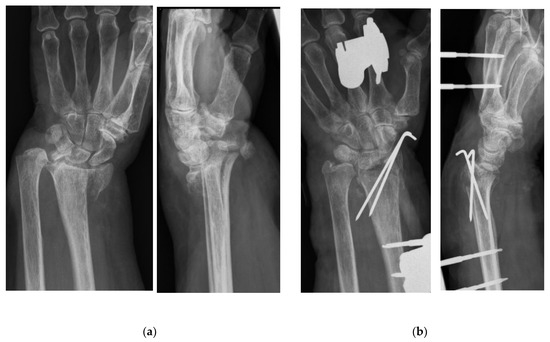

Wrist Hemiarthroplasty for Complex Intraarticular Distal Radius Fracture in a Patient with Manifest Osteoporosis

2. Case Presentation